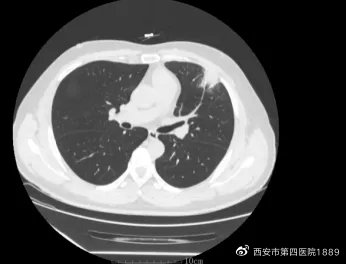

胸部CT平扫:右肺上叶后段胸膜下可见一微结节,直径约3mm;右肺中叶可见一实性结节影,大小约1.4cm×1.2cm

经医师询问,患者无发热、咳嗽咳痰、胸闷喘息、胸痛等呼吸系统症状;体格检查胸廓对称,呼吸频率正常,两肺触诊和听诊均阴性;血常规基本正常,肿瘤标志物未见明显异常。从胸部影像学(LDCT)来看,患者左肺上叶呈支气管周围分布,伴有晕征,考虑炎症可能性大,而右肺中叶病灶呈结节样,周围可见毛刺征和血管集束征,不能排除原发性肺部肿瘤可能。

患者按医嘱治疗后于2月26日复查,胸部CT可见双肺病灶明显吸收